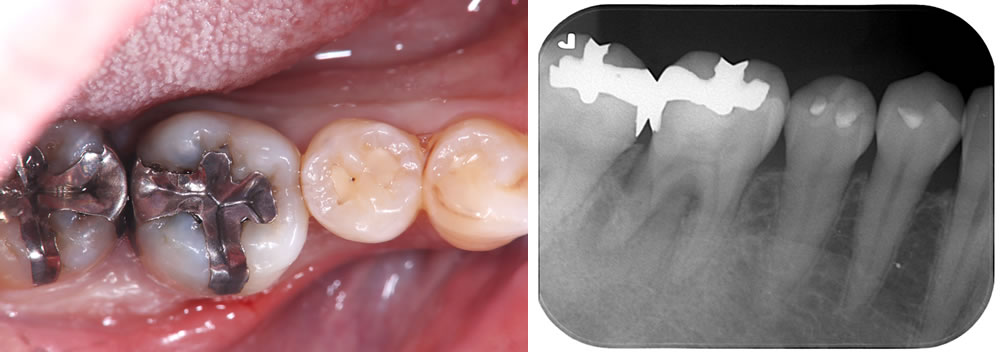

こちらの患者さまは、右下奥から2番目の歯が噛んだ時に痛いとの主訴で来院されました。

レントゲン写真にて、右下6番歯の歯根周囲に透過像を認めました。口腔内を確認したところ、メタルインレー下に二次う蝕を認めました。また、歯周ポケットは10mmと深く、歯根破折が疑われたため、補綴物を除去して精査することとなりました。

メタルインレーの除去

当該歯のメタルインレーを除去したところ、歯の内部に2次カリエス(虫歯の再発)を認めました。

う蝕検知液(虫歯部分に着色する薬液)を使用しながら、慎重に虫歯除去を行ったところ、遠心に歯根破折を確認しました。歯周ポケットが深かった部位と破折線が一致しており、このままつめ物を装着しても予後不良となる可能性があることを患者さまに説明したところ、抜歯とインプラントによる治療を希望されました。